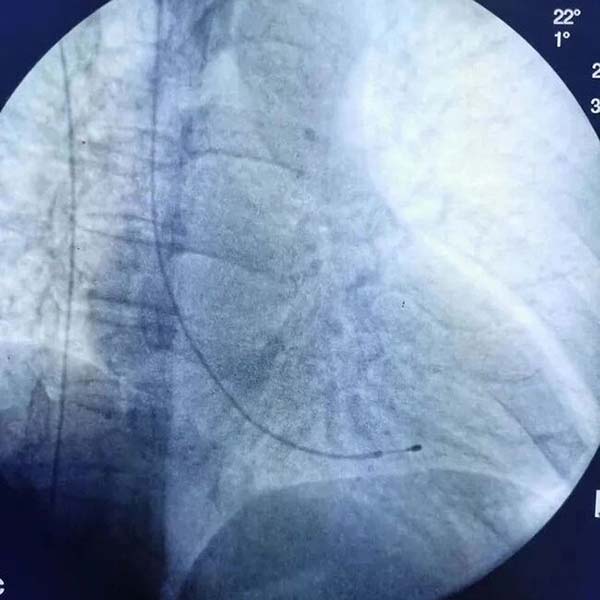

手术当日,心内科起搏团队主治医师刘滕飞经右侧颈内静脉顺利将临时起搏电极植入患者右心室间隔部,连接体外临时起搏器。随着起搏器启动,患者心率立即稳定在每分钟60次,血压、血氧饱和度等指标恢复正常。